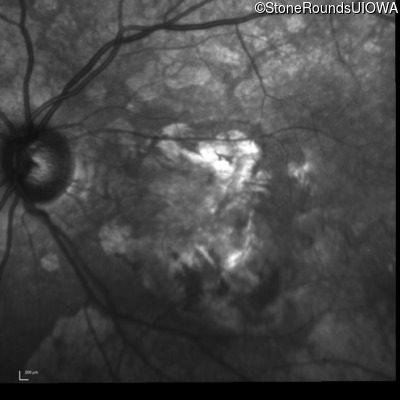

Infrared Fundus Photograph - Right - 20/160 -2

Exemplar